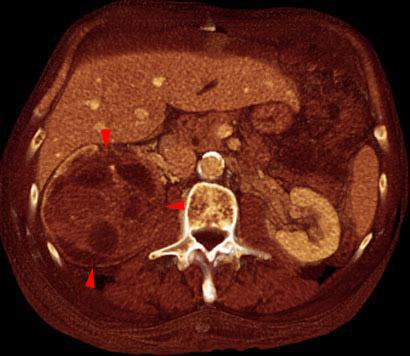

Tumor renal necrosado

VR seccional. Visión axial caudal. TC contrastado en fase venosa que muestra una gran tumoración heterogénea del riñón derecho, alternando zonas líquidas o necroticas junto a áreas sólidas (puntas de flecha)